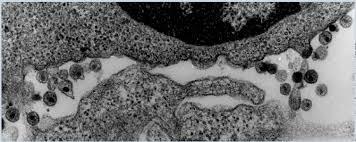

Profesor Charles Daguet, descubre la imágen del virus, y lo denomina LAV.